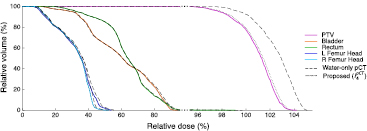

Dose calculations were performed for the water-only pseudo CTs and for the pseudo CTs obtained after four iterations. The DVHs displayed in figure 7 for a representative subject show a close agreement between the doses calculated from the reference and proposed pseudo CTs while larger differences are observed between the reference and water-only pseudo CTs. Boxplots showing the dose differences evaluated for several DVH points are displayed in figure 8. With the proposed method, for all the DVH points considered, the dose difference is on average less than ±0.15% for the PTV and all the OARs. With the water-only pseudo CT, a systematic bias is observed. For most DVH points, the dose difference is on average between 1.5% and 3%.

Figure 7. DVHs obtained for the reference CT (solid lines), water-only pseudo CT (dashed lines) and pseudo CT obtained after the fourth iteration of the proposed framework (dotted lines) in the PTV and OARs for a representative subject. Note the change in scale on the x-axis when the relative dose is higher than 95%.